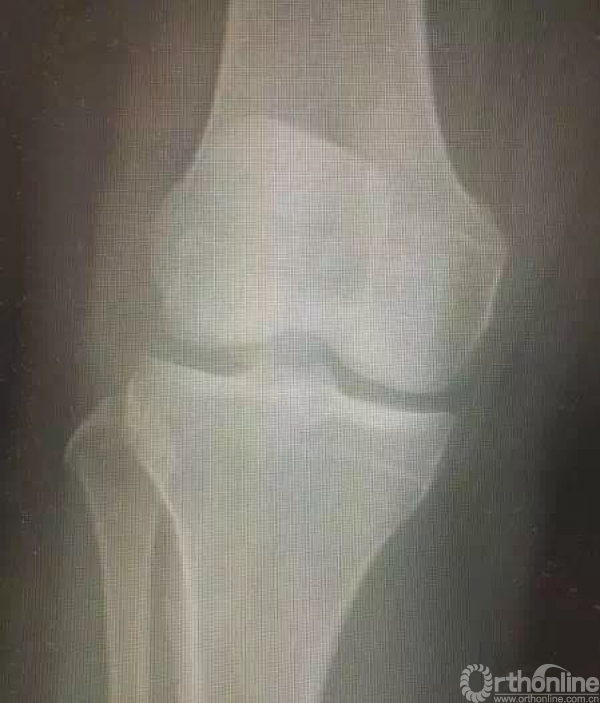

2.这例患者是否骨折?——该例病例为二分髌骨,并非髌骨骨折,发生率为8%,多数位于上外侧。